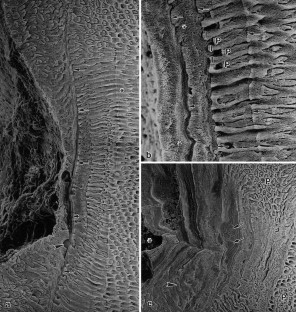

We studied the structural changes in the enamel of mandibular third molars of miniature pigs administered a daily oral dose of 2 mg NaF (approximately 0.9 mg of fluoride) per kg body weight (added to the feed) for 1 year. The treatment period covered most of the secretory stage and the entire post-secretory stage of amelogenesis of the M3. The enamel of the molars from the fluoride-fed pigs appeared opaque and chalky, and the erupted portions were stained brown. The underlying histopathological change was a pronounced subsurface hypomineralization of the enamel beneath a thin surface rim of higher mineral content. This enamel hypomineralization was attributed to a fluoride-induced impairment of the process of enamel maturation. The most conspicuous finding in the fluorotic enamel was the presence of numerous pit-type hypoplastic defects, denoting a marked fluoride-induced disturbance also of the secretory stage of amelogenesis. Microradiography and scanning electron microscopy revealed an enhanced incremental pattern in the outer enamel of the fluorotic molars. Typically, the bottom of larger hypoplastic defects was underlain by a broad, grossly accentuated incremental line. Occurrence of larger hypoplasias was further associated with the presence of aprismatic enamel, the formation of which was attributed to a loss of the prism-forming (distal) portion of the Tomes’ processes of secretory ameloblasts. The findings in the miniature pigs closely parallel earlier observations on fluorotic enamel of free-ranging deer and wild boar from fluoride-polluted areas.

Fig. 7a–c

Fig. 8a,b